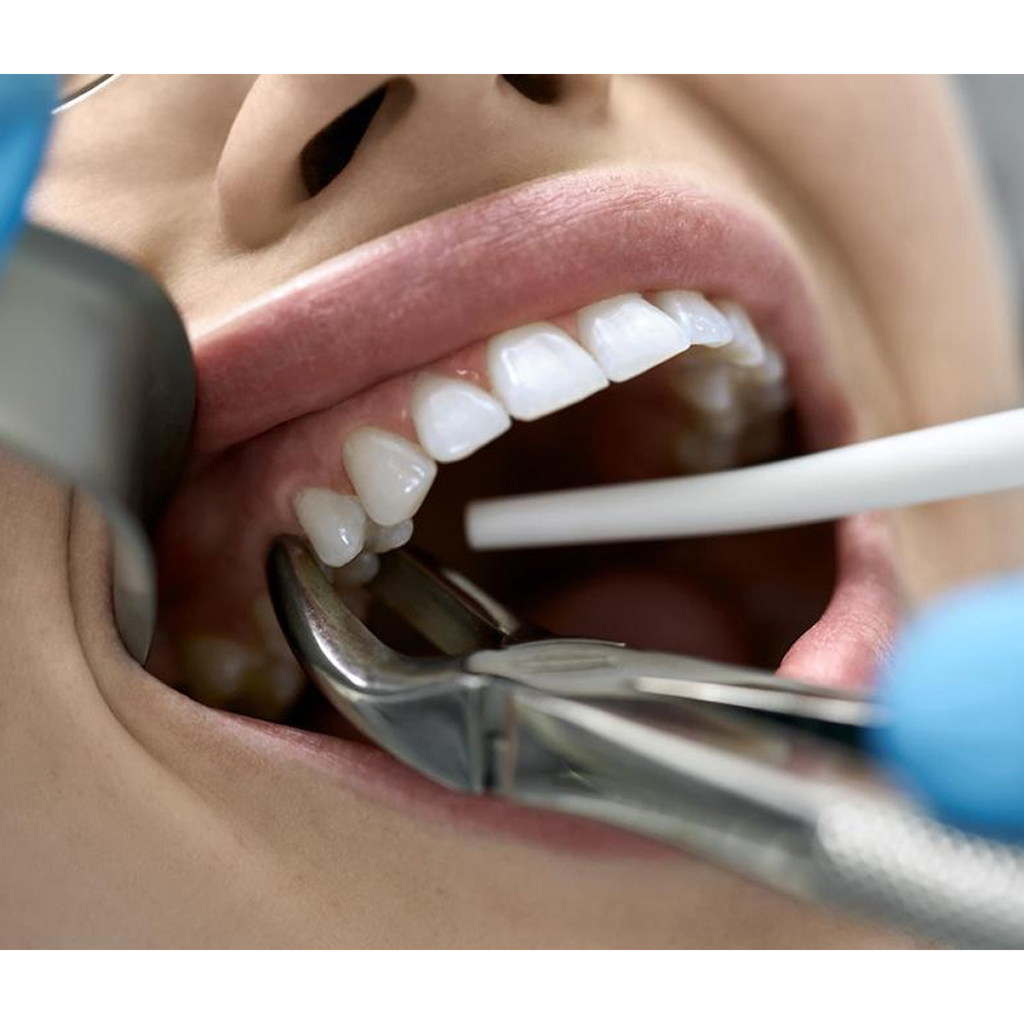

Pedo Extraction Forceps: These specialized forceps are designed to extract deciduous (baby) teeth gently. They have smaller, anatomically adapted beaks that fit comfortably around the smaller roots of baby teeth, reducing the risk of trauma during extraction. The handles are designed for easy grip and better control, ensuring a safe and efficient extraction process.

Pedo American Forceps: These forceps are designed to grip and extract deciduous teeth that are mobile or need removal. They have unique beak designs that cater to the varying shapes and sizes of baby teeth, providing a secure hold for extraction while minimizing any discomfort for the child.